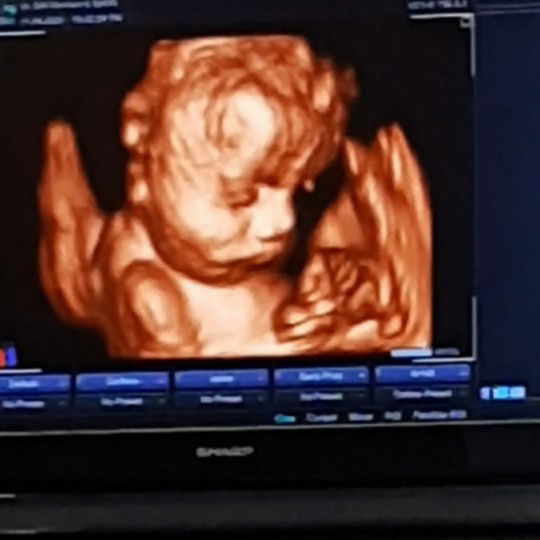

janin ngumpet atau blm terlihat 8week

Saya bun, 8week di usg belum terlihat, auto panik dong, lngsung di usg transvagina alhamdulillah sudah terlihat dan sudah ada detak jantungnya juga.

Saya usg 8 week belum keliatan janinnya bun, disuruh balik lagi pas usia 10 week sudah ada janin+ detak jantungnya bun

8week harusnya udah ada janin walau terlihat memang kecil bgt..coba USG transvaginal untuk memastikan..